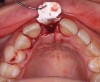

The right central incisor was removed atraumatically (Figure 3) without elevating a buccal flap. The presence of the buccal bone dehiscence was confirmed with the use of a periodontal probe. Measurements from the free gingival margin to the crest of the buccal bone and a horizontal assessment of the defect size indicated a dehiscence that was 8-mm tall and 5-mm wide. The distance from the free gingival margin to the most apical point in the socket was 10 mm.

Fig 3. Atraumatic extraction of central incisor.

Figure 3